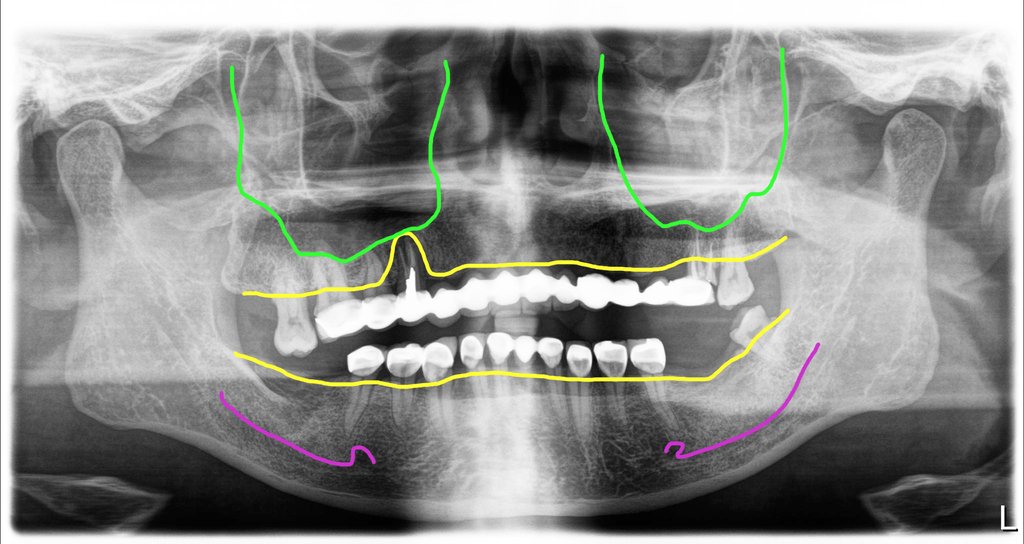

이 분도 브릿지를 제거했을 때 대부분의 치아들이 썩어 있어 모두 제거를 했고, 오른쪽에 한개 남아있는 치아는 아래로 너무 떨어져 이용할 수 없어 제거를 같이 했습니다.

아래는 보철이었지만 롱브릿지가 아니어서 속에 치아들이 썩지 않아서 다시 크라운 치료를 하는 식으로 치료를 진행하기로 했습니다.

이 분은 잇몸질환으로 치아를 뽑지 않았기 때문에 비교적 뼈의 모양이 잘 유지되어 있어서 결과가 더 예쁜 것 같아요.

이 분은 수술하신 지 4년 정도 되셨고 치료완료후 미국에서 관리하시다가 올해 한 번 검진 오셨는데 상태 아주 좋았습니다. 계속 잘 사용하시길 바라는 마음입니다.